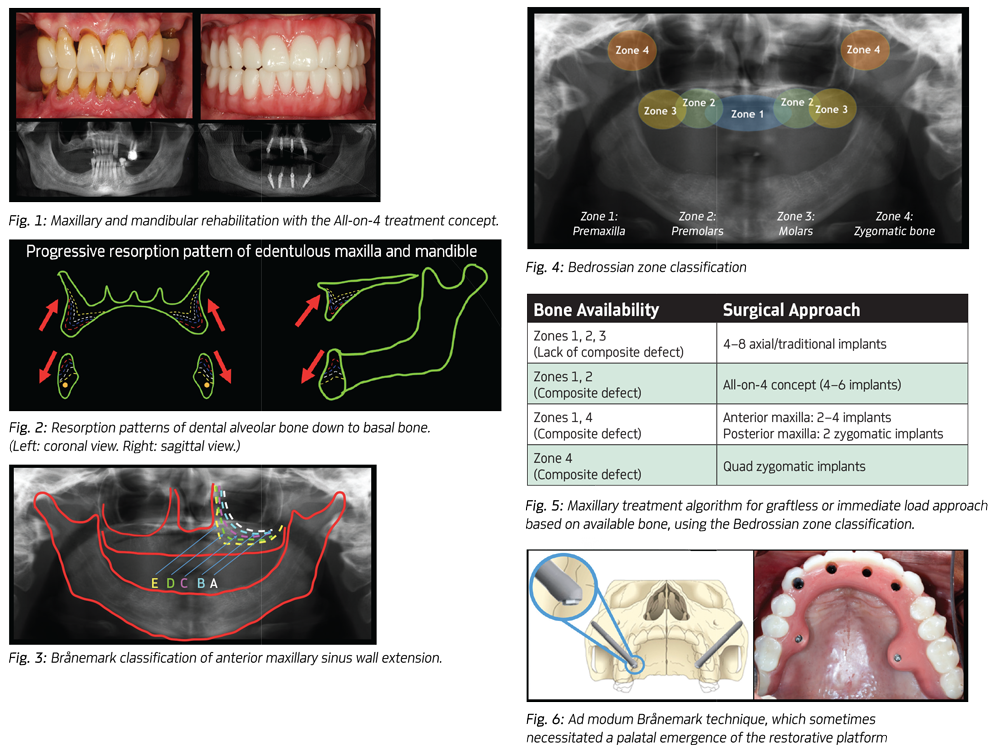

Today, the All-on-4 treatment concept is considered a predictable and efficient treatment used daily to rehabilitate edentulous patients and those with a terminal dentition (Fig. 1).

The loss of teeth in the maxilla leads to a progressive resorption of the residual alveolar ridge. This pattern of bone loss proceeds in a superior/posterior and medial/palatal direction (Figs. 2 and 3). This leads to changes in the facial morphology, giving a sunken-in, collapsed and aged appearance to the face without appropriate lip support. The resorption pattern may lead to a shallow or flattened palatal vault and lack of adequate vestibular depth. Additionally, over time patients often develop significant hyperpneumatization of the maxillary sinuses that extends anteriorly to the premaxilla.

When evaluating a patient with a terminal maxillary dentition or one who is already edentulous, radiographic screening begins with a panoramic image. Potential available bone sites are identified using the Bedrossian zones (Fig. 4, p. 56). Careful clinical evaluation of the patient is performed to determine if there is a missing tooth-only defect or a composite defect. This evaluation includes determining the appropriate incisal edge position, need for lip support and the appropriate vertical dimension of occlusion. The need for bone-reduction or alveolectomy is also predetermined to provide for the necessary prosthetic component space, hiding the transition-zone and creation of a hygienic and cleansable prosthesis (Fig. 5).

The original Brånemark protocol dictated that the zygomatic implant would have quad-cortical stabilization based on a trajectory that proceeded from the palatal side of the residual alveolar process through the maxillary sinus, with subsequent entry into the zygomatic bone, ultimately exiting through the superior/lateral cortex of the zygoma. The main drawback from this approach was often a significant palatal emergence of the implant restorative platform, which then resulted in bulky prostheses, made hygiene more difficult and sometimes created difficulty with speech (Fig. 6).